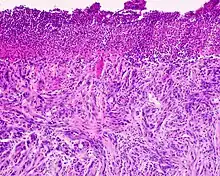

Desmoplastic melanoma is a rare cutaneous condition characterized by a deeply infiltrating type of melanoma[2]: 696 with an abundance of fibrous matrix.[3] It usually occurs in the head and neck region of older people with sun-damaged skin.[3] Diagnosis can be difficult as it has a similar appearance to sclerosing melanocytic nevi as well as some nonmelanocytic skin lesions such as scars, fibromas, or cysts.[3]